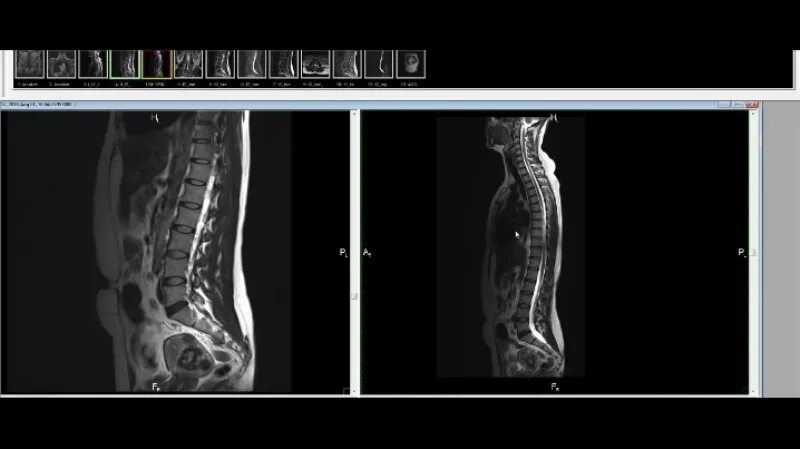

Перед мрт позвоночника можно кушать